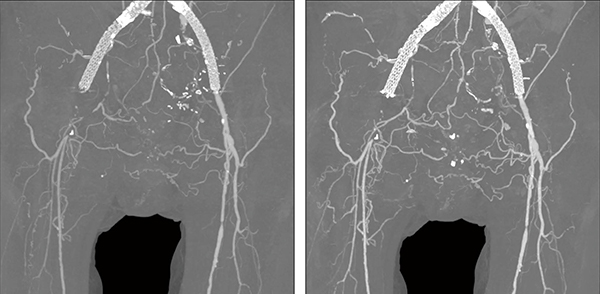

図2 下肢動脈造影

CTDIvol=3.6mGy、DLP=423.1mGy・cm

AiCE-i再構成により、低被ばくで、かつ末梢の血管まで描出能が向上している。